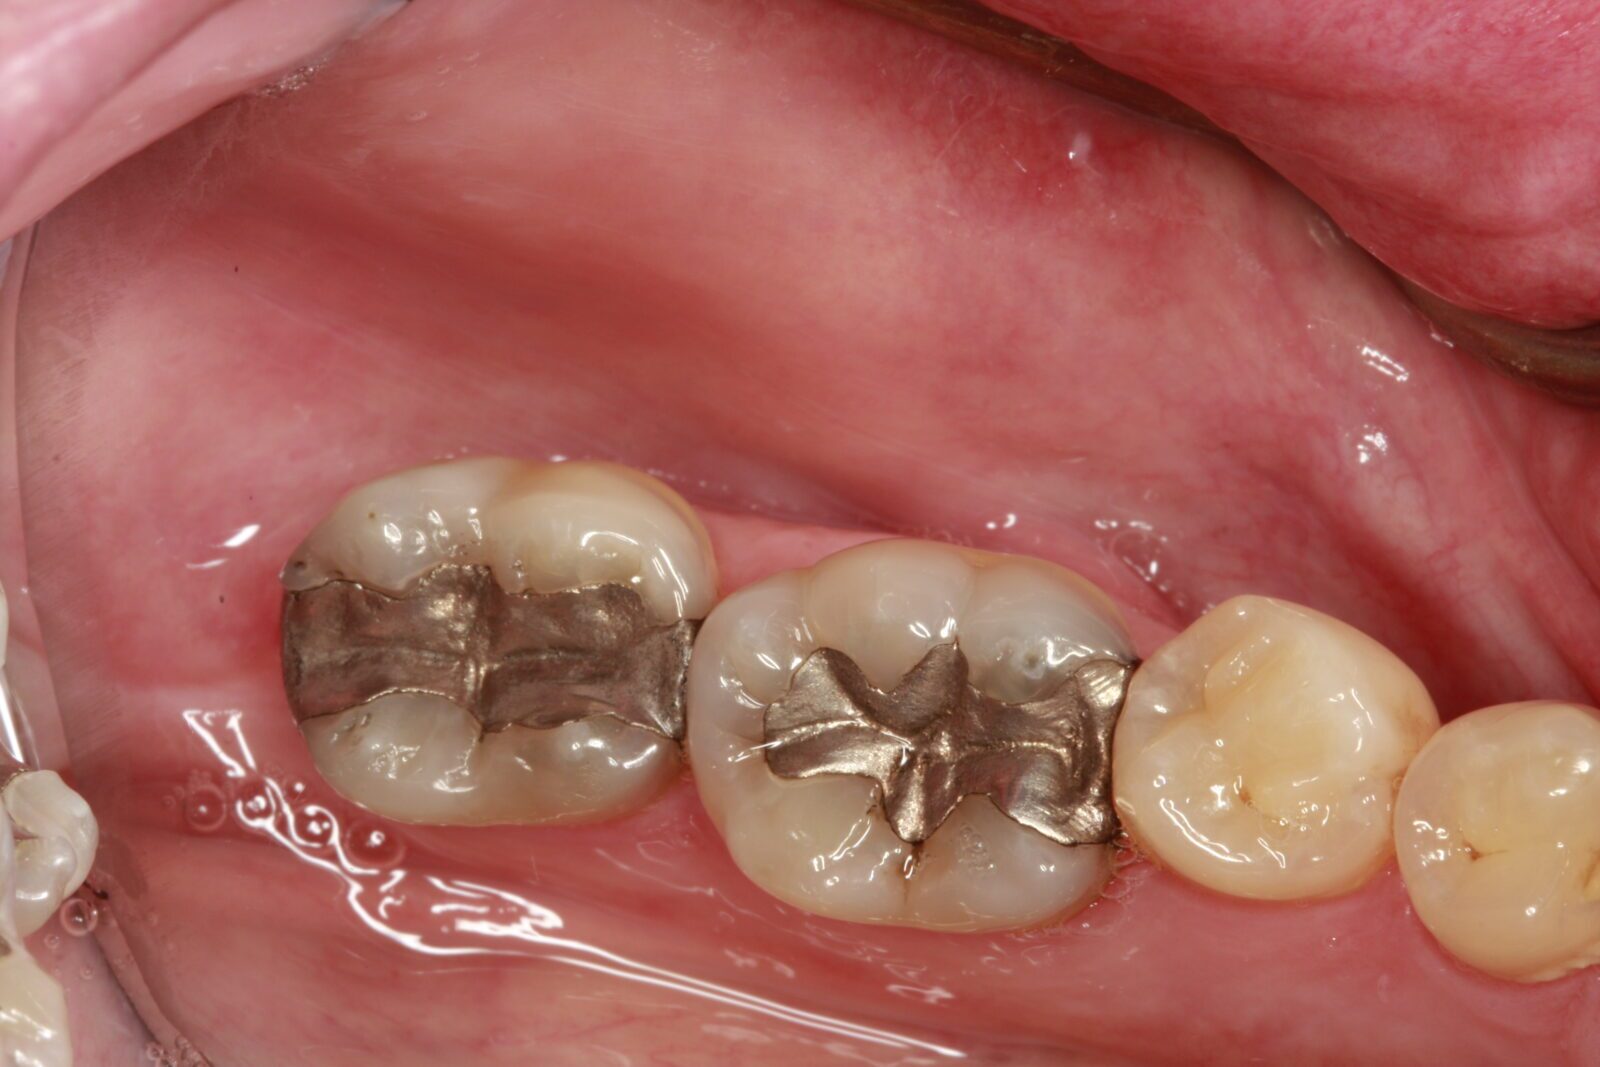

2. Metal Crowns

Metal crowns, often made from gold, platinum, or palladium alloys, provide exceptional strength and durability. They are typically used for molars and teeth that are not highly visible.

• Aesthetics. Metal crowns are not as aesthetically pleasing as porcelain crowns due to their metallic color.